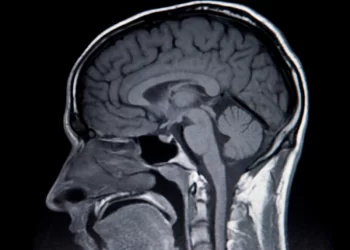

Implante cerebral permite a un hombre con ELA hablar y cantar con su “voz real”

Un hombre con una discapacidad grave del habla puede hablar expresivamente y cantar gracias a un implante cerebral que traduce su actividad ...